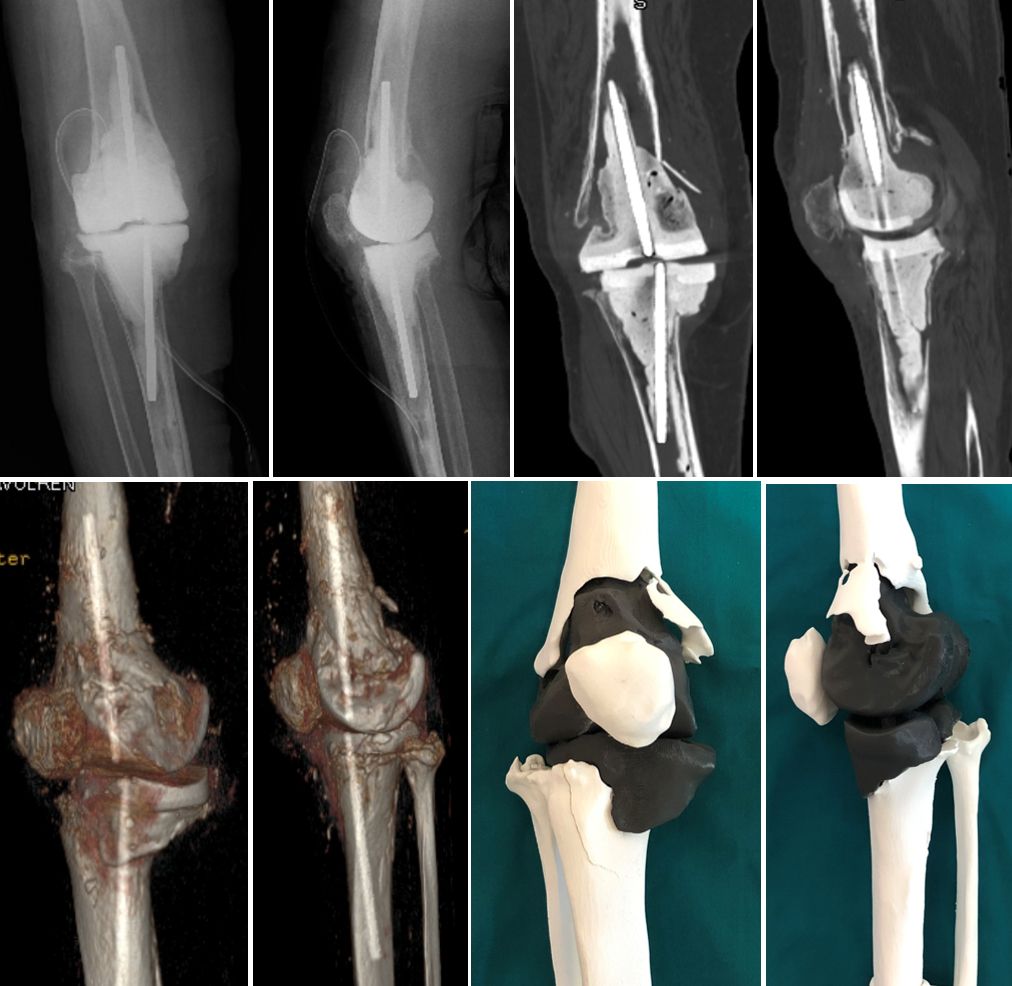

The development of three-dimensional (3D) printing technology is proposed for better planning of complex revision surgery. Regarding preoperative revision planning, conventional radiographs often underestimate the degree of bone loss, while computed tomography (CT) can provide additional details, but the surgeon is limited in his or her ability to clinically translate this information into surgical execution (Fig. 1).

3D technology has already been used for complex hip revisions in our department for many years. In a recent published study we compared the diagnostic accurracy between 3D printed model with 3D CT reconstruction for pelvic discontinuity [19] (Fig. 2). For knee revision surgery based on a preoperative CT scan, a 1:1 3D plastic knee model is made, including the cement spacer or implant to be removed in a different colour and separated from the virtual bone (Fig. 3).

The 3D model accurately reproduces all the bony landmarks that will be used for surgery and can be cut and manipulated with the surgical instruments. The model can then be sterilised, marked and taken into the operating room to help orient the surgeon and placing the components. The advantage of 3D printed models is demonstrated by bone loss after infection with Case 1 (Figs. 13 and 14) and after aseptic loosing with Case 2 (Figs 15 and 16).

Case 3 further demonstrates the advantages of 3D models for a 77 years old woman after two stage revision for septic loosening of a cemented primary implant 12 years ago. After reinfection and several AB spacers, bone stock on both femoral and tibial sides was compromised (see also fig. 1). Re-Revision surgery was planned with RHK using cones for both the tibia and femur (Figs 18 and 20).